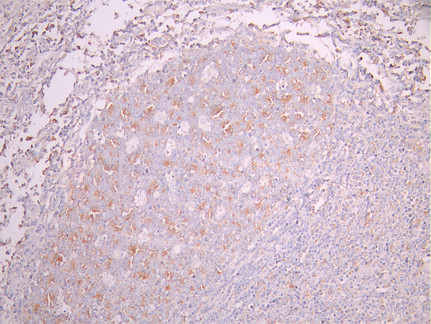

• IHC image of CSB-RA270243A0HU diluted at 1:100 and staining in paraffin-embedded human breast cancer performed on a Leica BondTM system. After dewaxing and hydration, antigen retrieval was mediated by high pressure in a citrate buffer (pH 6.0). Section was blocked with 10% normal goat serum 30min at RT. Then primary antibody (1% BSA) was incubated at 4°C overnight. The primary is detected by a Goat anti-rabbit polymer IgG labeled by HRP and visualized using 0.05% DAB.